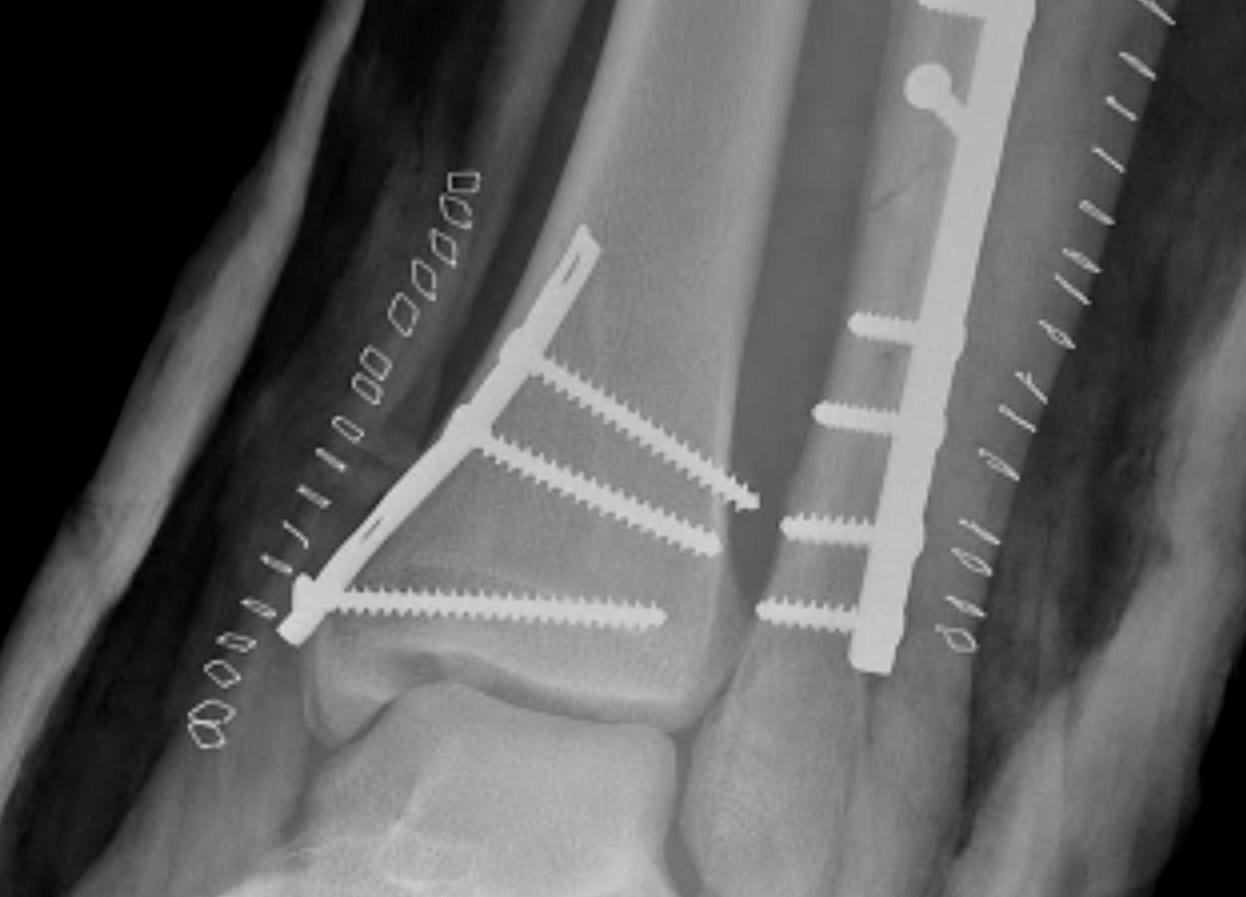

Fracture patterns

| Lateral malleolar fractures | Medial malleolar fractures | Bimalleolar fractures | Trimalleolar fractures |

Weber A - below syndesmosis Weber B - at syndesmosis Weber C - above syndesmosis |

Uncommon |

Fibular + medial malleolus Bimalleolar equivalent - fibular + deltoid ligament Fibular + posterior malleolus |

Fibular fracture + Medial malleolus fracture + Posterior malleolus fracture |